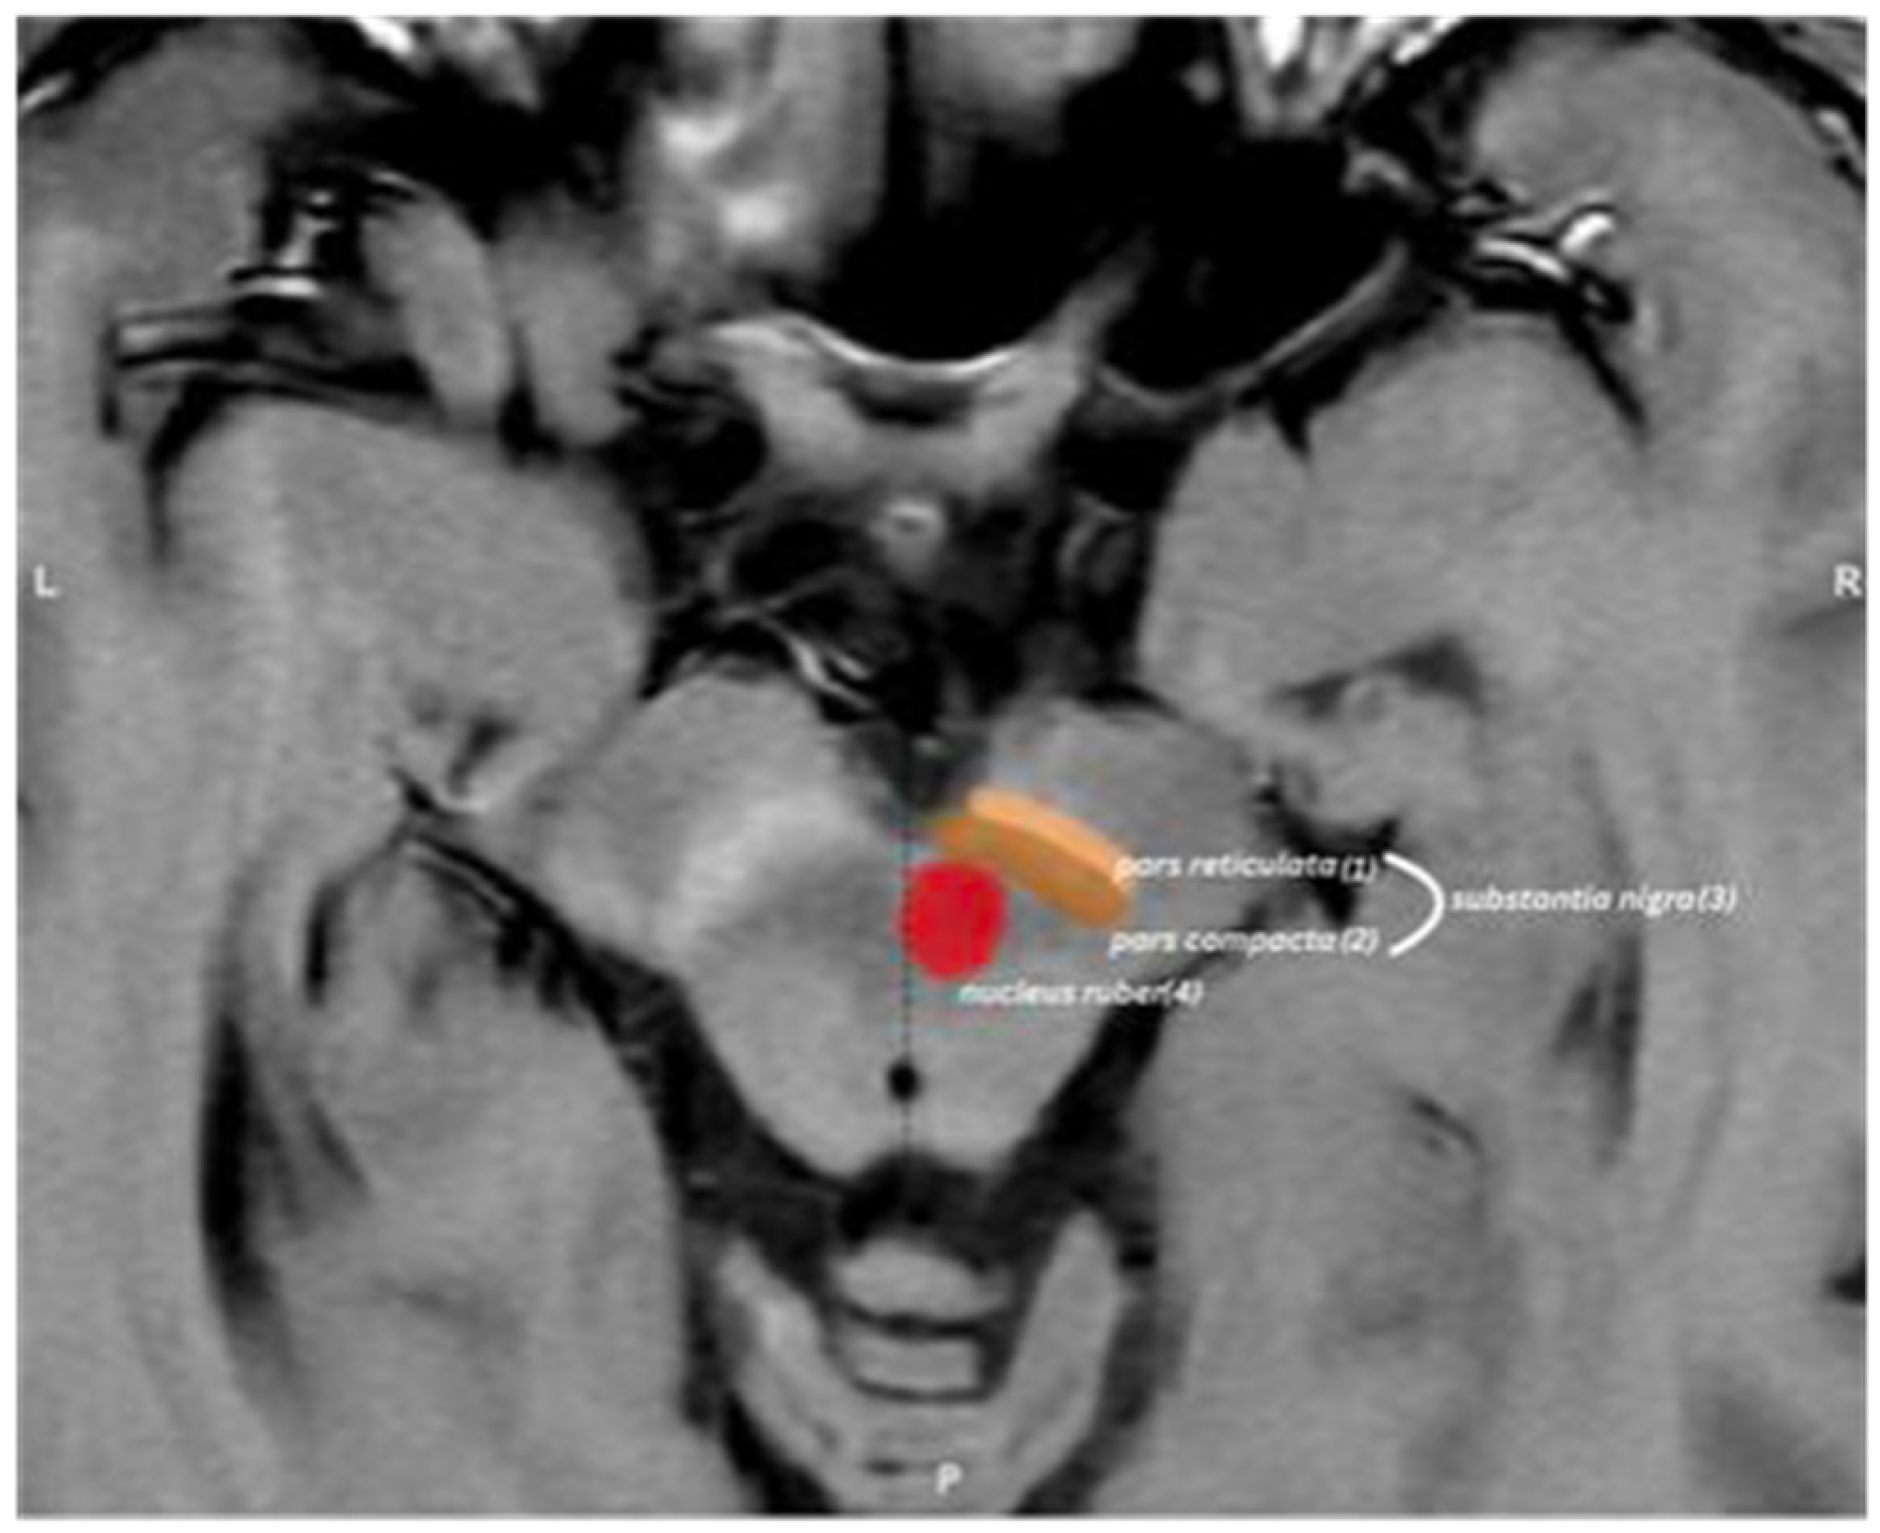

2.4.1. Semi-Automated Segmentation

2.4.2. Mean Midbrain Intensity Quantification

2.4.3. Volume Measurement

2.4.4. Volume Correction